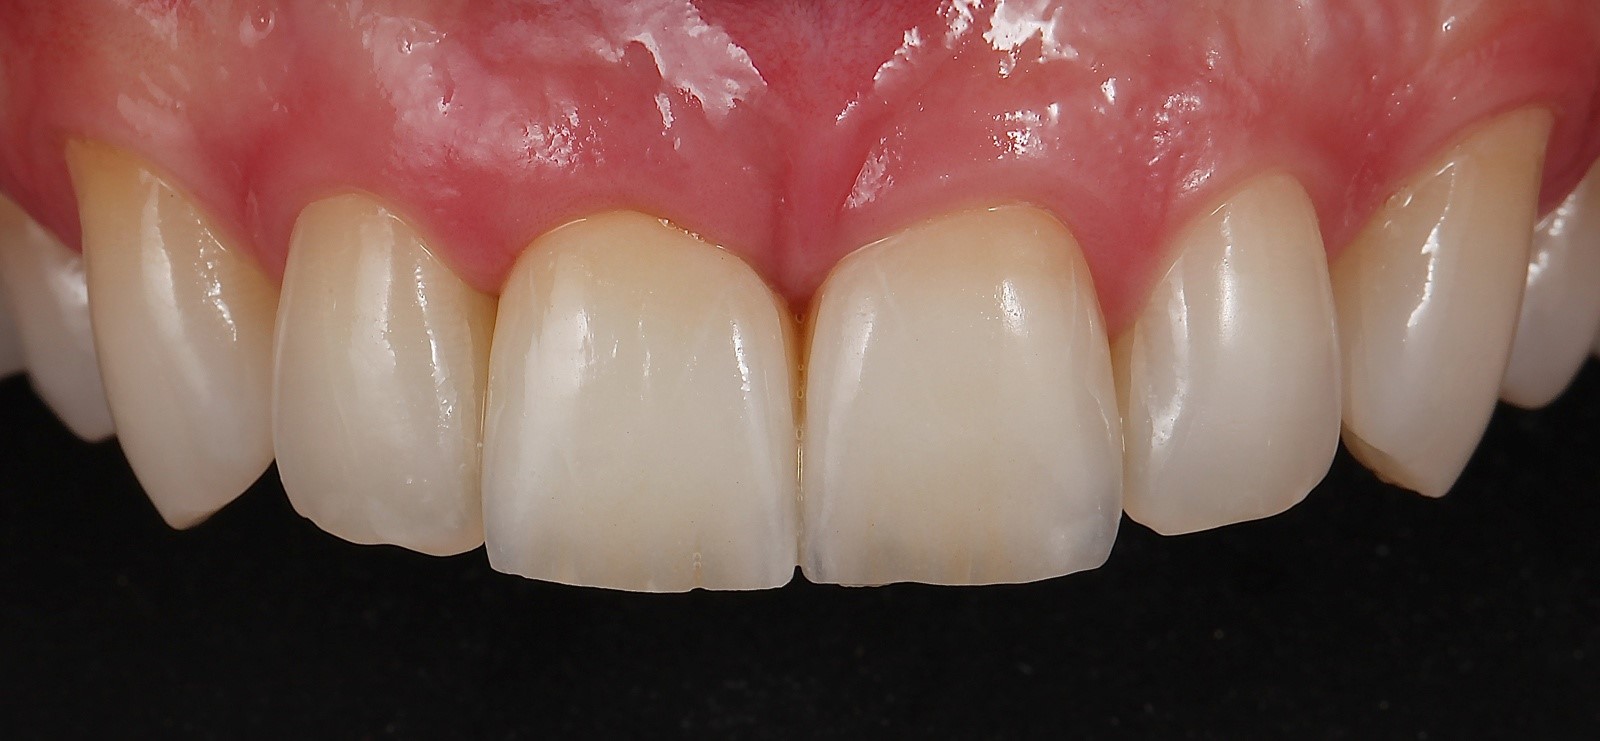

Fig 15. A tunneling procedure with a small connective tissue graft was performed to establish extra soft tissue with a thickened biotype.

Figure 15